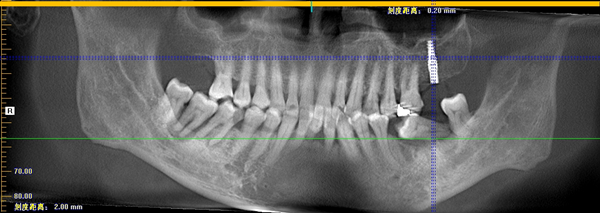

但随着年纪增大, 我牙齿逐渐松动脱落, 更糟糕的是我喜欢咬硬东西, 牙齿磨损得厉害,有一次不小心就把牙齿给咬断了。不仅痛,还刺激到牙神经很不舒服。拔了几颗牙齿之后,吃东西咀嚼都很艰难,味道也跟之前完全不同了。档期满满的,缺牙问 题 一 直 没有时间解决,让我非常困扰。牙齿缺失随之而来的是说话漏风、台词都念不准,我担心无法呈现最完美的一面给观众。

刚考虑种牙的时候,我也跟大家一样各种担忧,担心种牙痛不痛、 安不安全,等等……作为公众人物,我经常有机会访问国内的医疗机构, 在综合对比后我发现,麦芽的各项设施和技术都处于行业领先水平,设备齐全,环境干净,最重要的是他们还拥有一支由硕博专家领衔的医疗团队。

我对麦芽专家团队很有信心, 所以整个过程是全然地放松。麻药注射后我就感觉自己的嘴角慢慢失去知觉,感觉就是喝一杯咖啡的时间吧就种好了,后来我问经纪人,她说只用了8分钟!